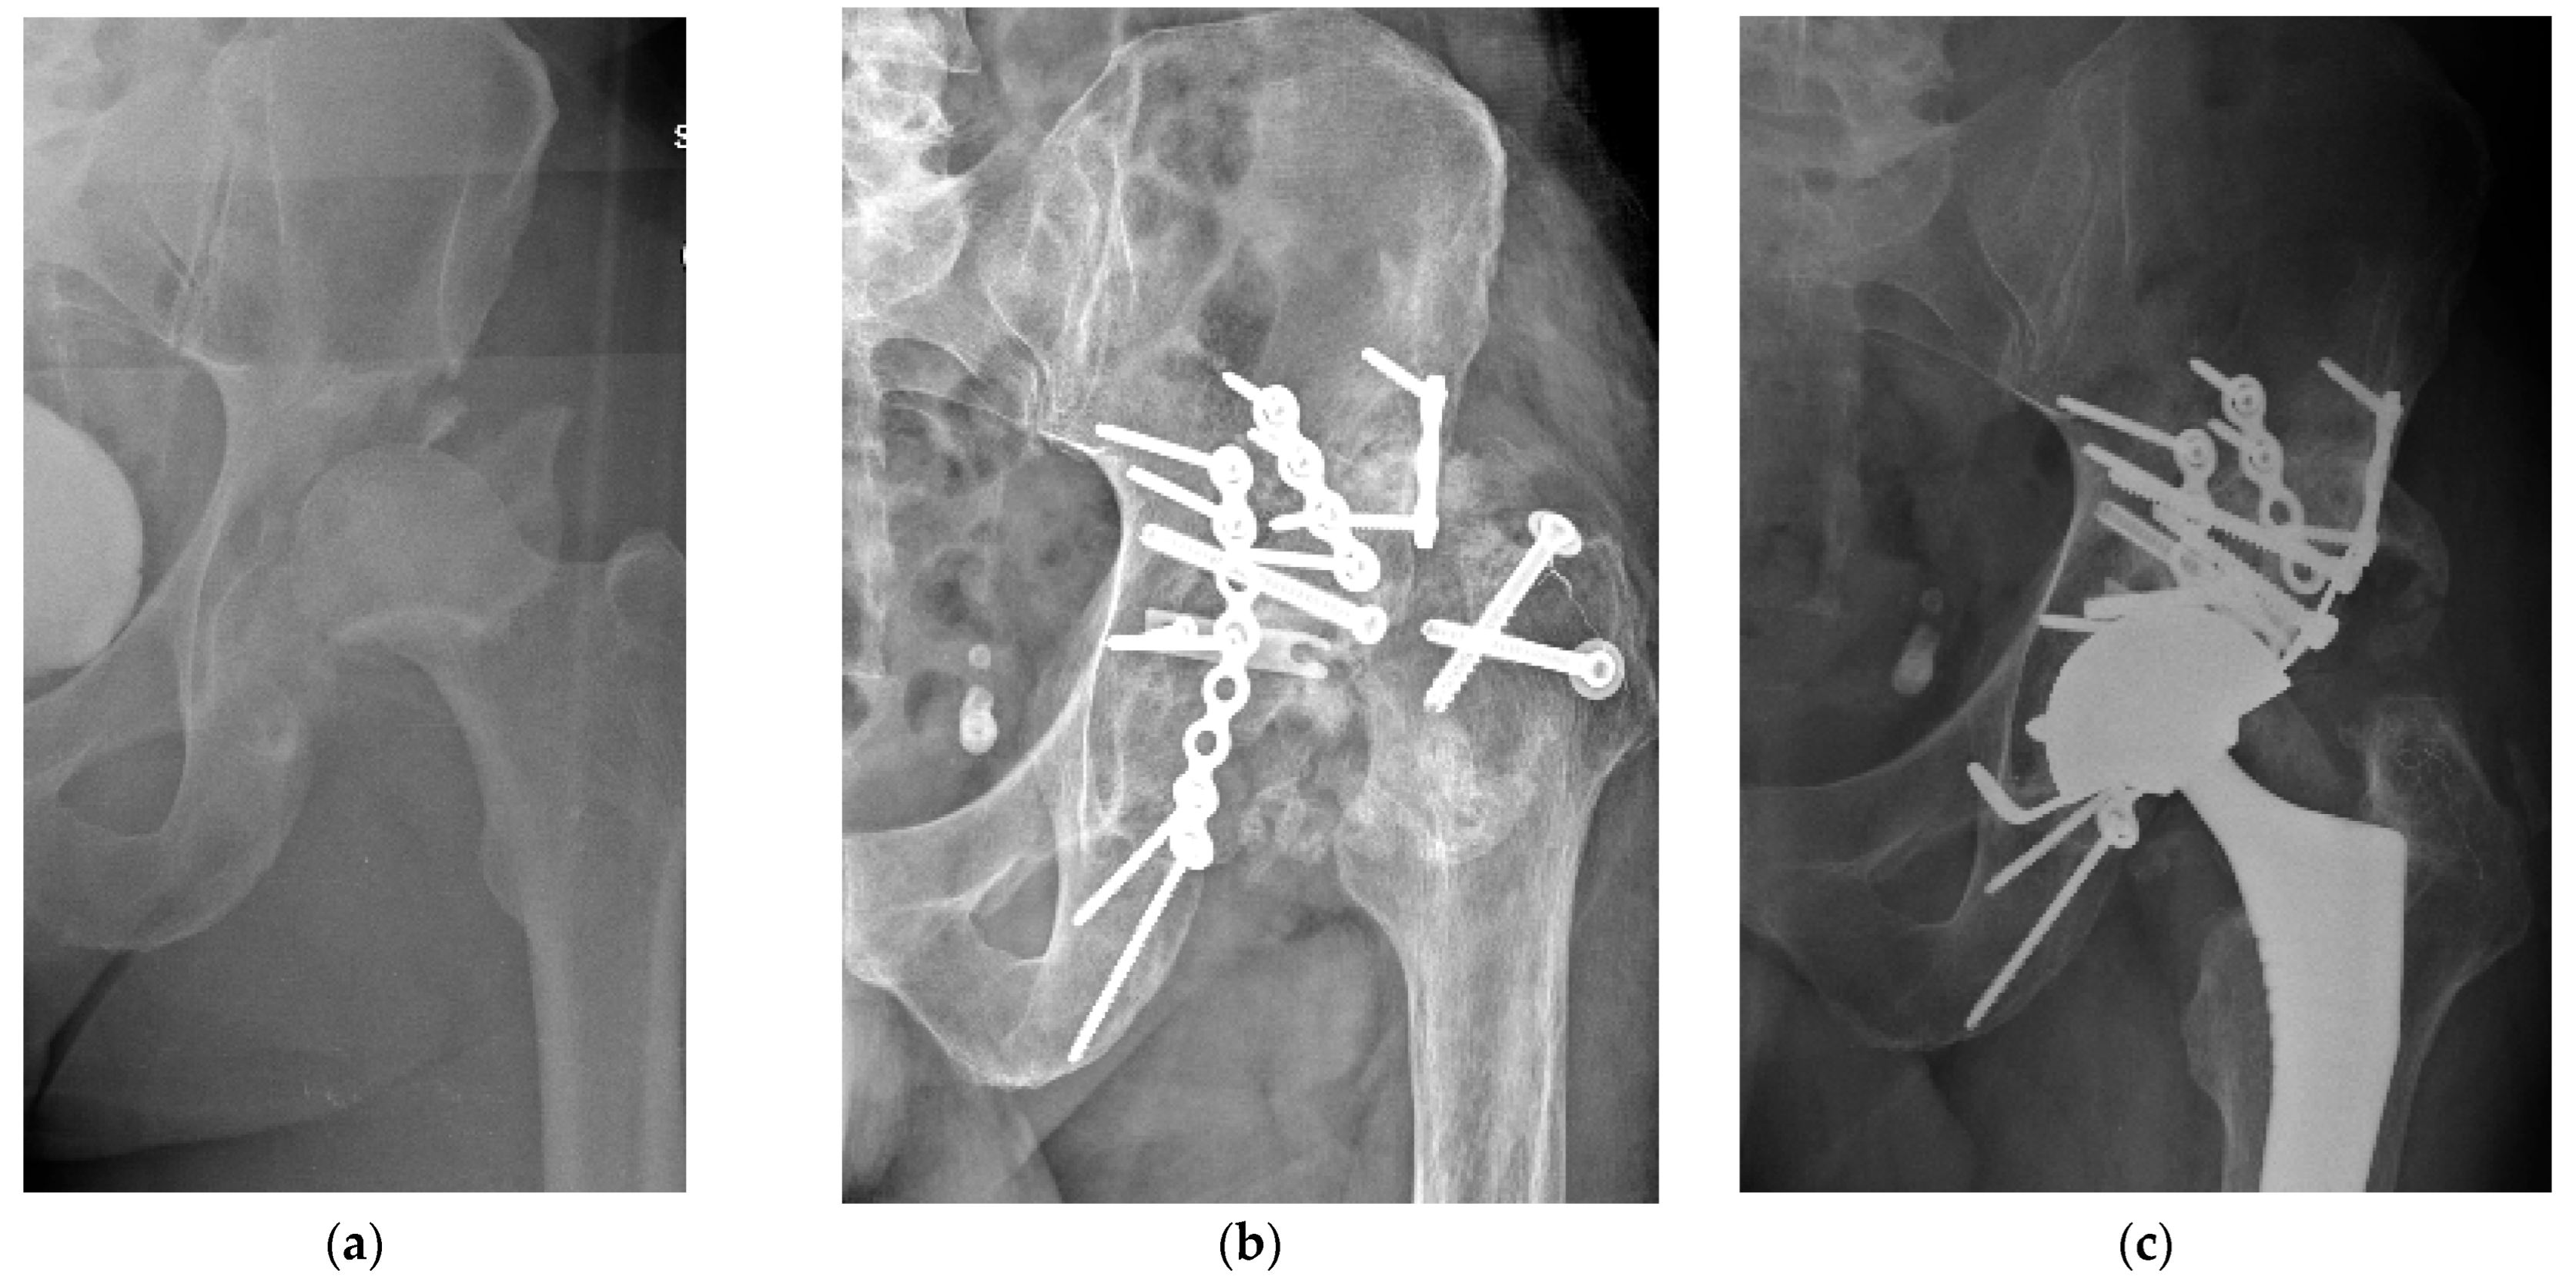

4.2. Late THA, Failure of Previously Operated Acetabular Fractures

4.3. Acute THA in Acetabular Fractures